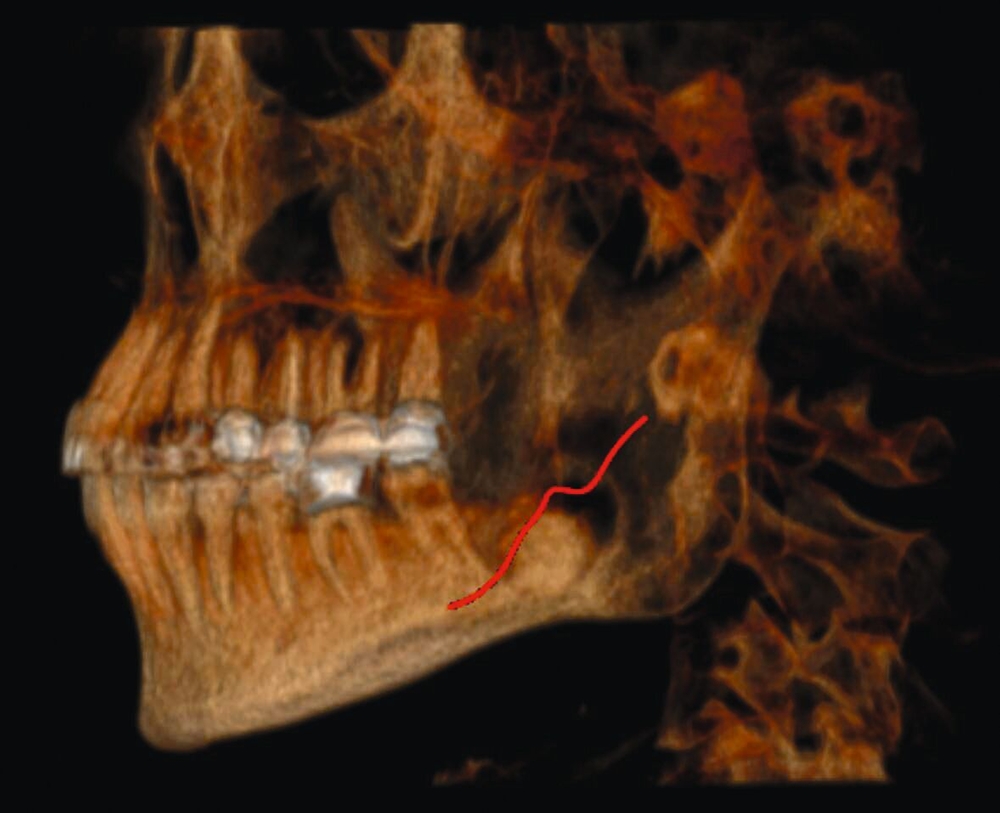

Eine 55-jährige, allgemeinanamnestisch gesunde Patientin stellte sich auf Überweisung ihres Hauszahnarztes mit einer unklaren Veränderung im Bereich des linken Kieferwinkels in der Klinik für Mund-, Kiefer- und Gesichtschirurgie des Universitätsklinikums Freiburg vor. Der Befund war bei einer Routinekontrolle in einer Panoramaschichtaufnahme (OPG) aufgefallen (Abbildung 1). Weitere Voraufnahmen existierten nicht. Radiologisch kam eine intraossäre, sklerotische Raumforderung mit zirkulärem, aufgehelltem Randsaum und überlagertem Nervus alveolaris inferior zur Darstellung. Klinisch bot sich ein unauffälliger Befund ohne knöcherne Auftreibung des Unterkiefers und mit blander Mukosa. Alle Zähne im linken Unterkiefer waren vital, die Sensibilitätstestung im Innervationsgebiet des linken Nervus alveolaris inferior zeigte sich regelrecht. Die Okklusion war habituell, die Mundöffnung ungestört.